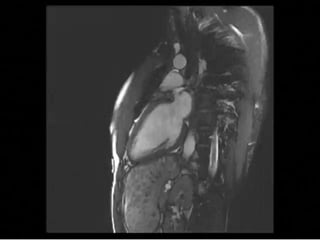

Cardiac amyloidosis

• DE-MRI shows diffuse LV hyper enhancement

• Subendocardium preferentially involved not limited

to arterial territory

Cardiac amyloidosis • DE-MRIshows diffuse LV hyper enhancement • Subendocardium preferentially involved not limited to arterial territory • Difficult to detect mild amylodosis

• #83 Renal failure progressive dyspnea on exertion. A, CMR reveals left ventricular hypertrophy with severe biventricular systolic dysfunction (four-chamber long-axis cine systolic image). B, Matching LGE imaging shows rapid washout of the contrast agent from the blood pool with diffuse intramyocardial LGE of the septum, subendocardial LGE of the inferior wall, and diffuse atrial LGE (black arrows). This pattern is consistent with amyloidosis.